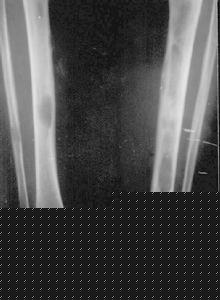

纤维性骨炎[1]是由于慢性肾衰继发性甲状旁腺功能亢进,引起的高转运型骨病。主要病因是继发性甲状旁腺功能亢进,使甲状旁腺增生、功能亢进,导致患者低血钙、高血磷,特别是二羟胆骨化醇的缺乏,晚期骨骼病变,皮肤瘙痒,自发性肌腱断裂,软组织钙化等。临床上主要表现为纤维性骨炎的病理改变。